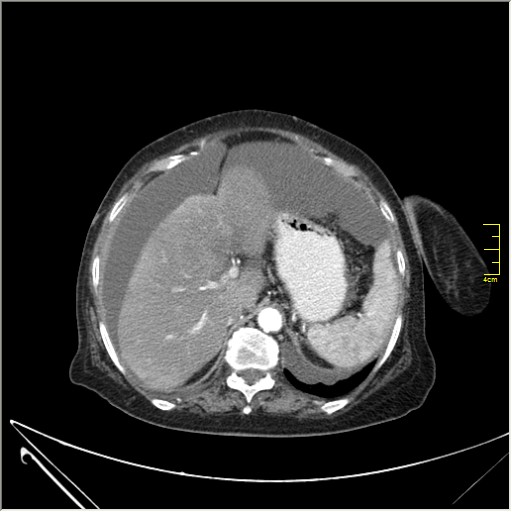

Женщина 72 года. Поступила с жалобами на вздутие живота. После осмотра хирургом, была сразу направлена на КТ брюшной полости.

Итак, асцит с объёмным образованием таза. В данном случае можно быть более конкретным, у пациентки неоплазия правого яичника с региональной лимфаденопатией (увидели?) и выраженным асцитом, характерным именно для злокачественных опухолей яичников. Пациентка оперирована ( операция Вертгейма); диагноз верифицирован: аденокарцинома правого яичника (серозная). Направлена к онкологу для дальнейшего лечения.